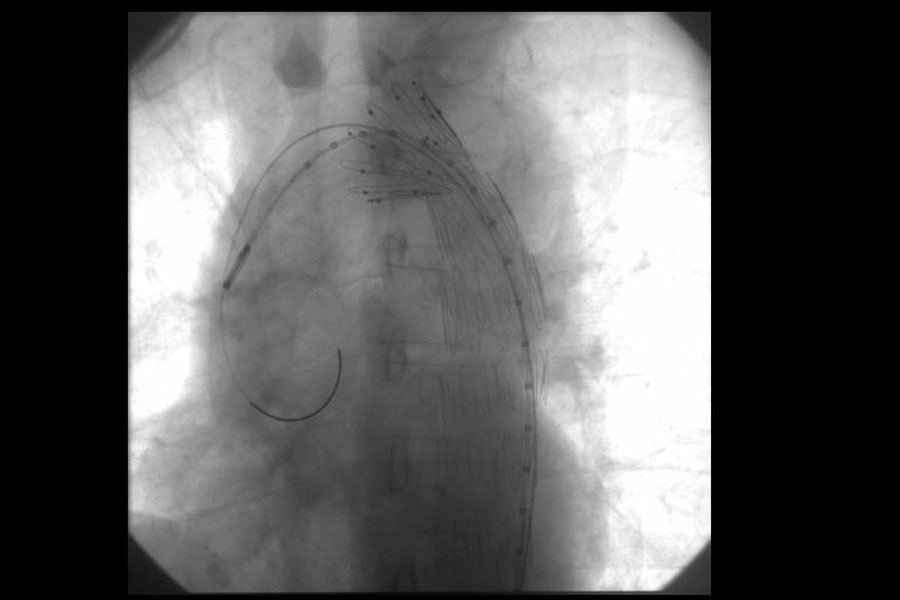

EVAR

Abdominal (Photo & Video Gallery)